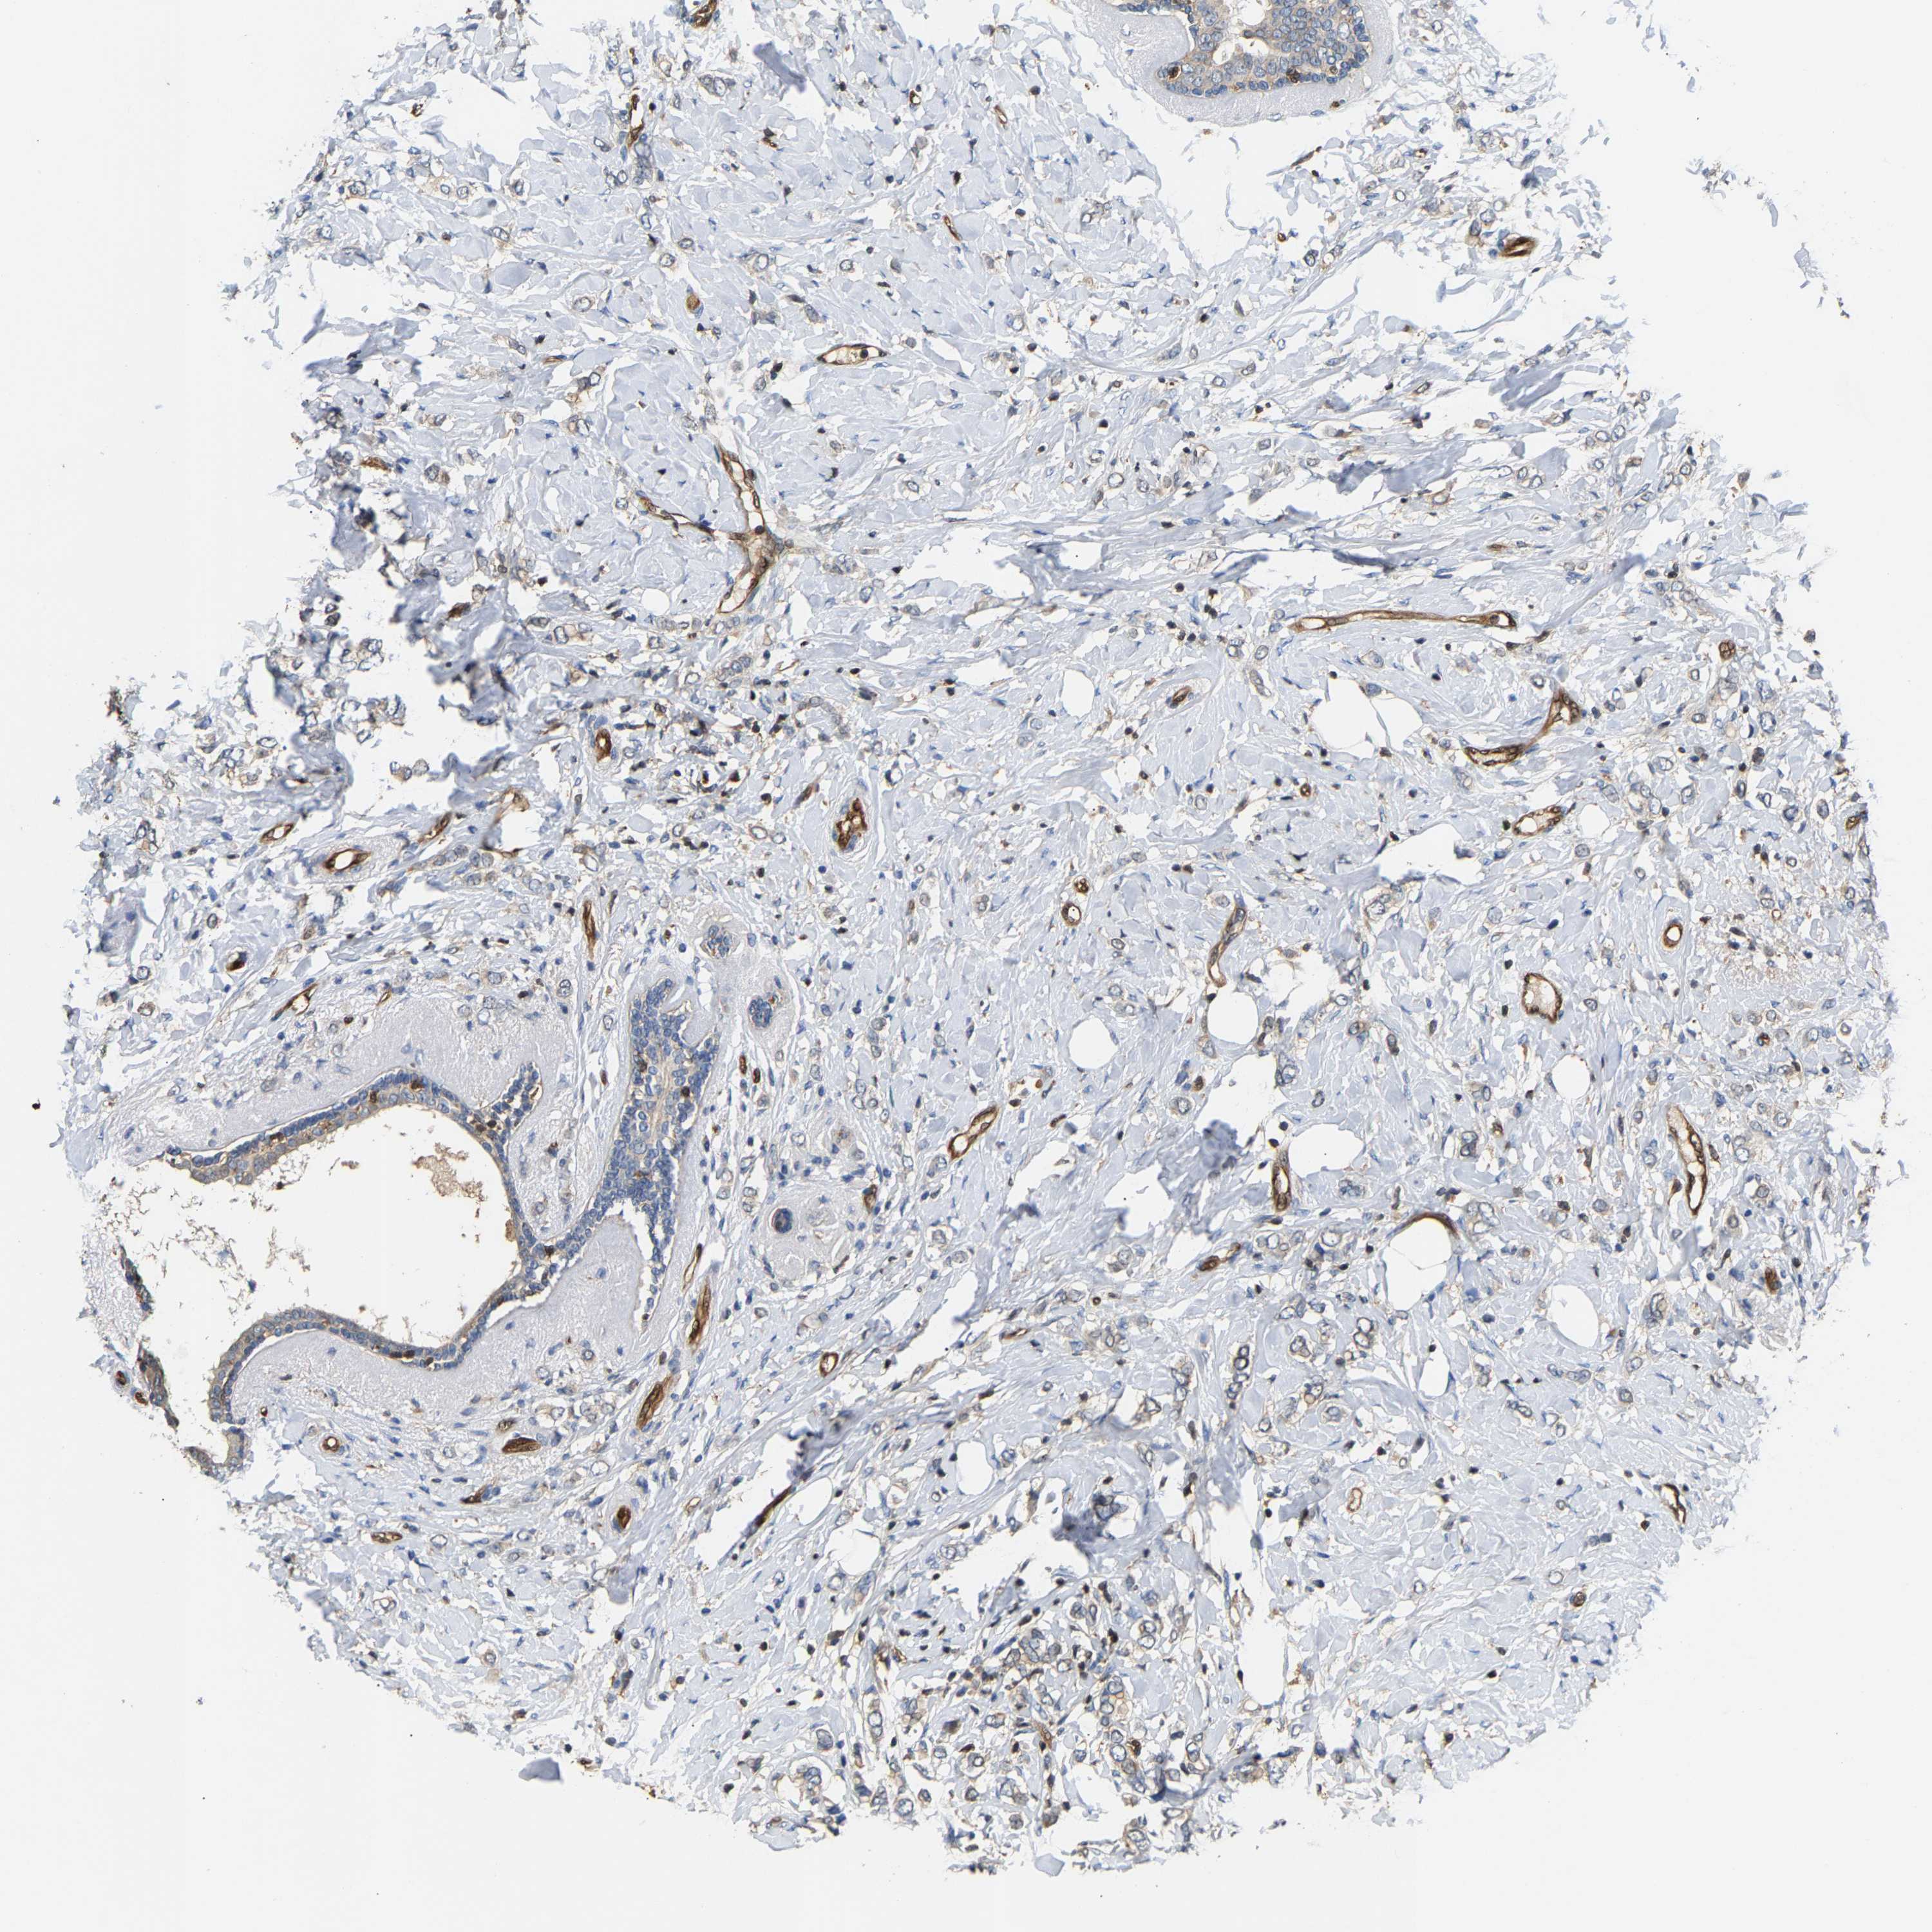

CANCER BREAST CANCER Show tissue menu

BRCA TCGA BRCA VALIDATION PROTEIN EXPRESSION